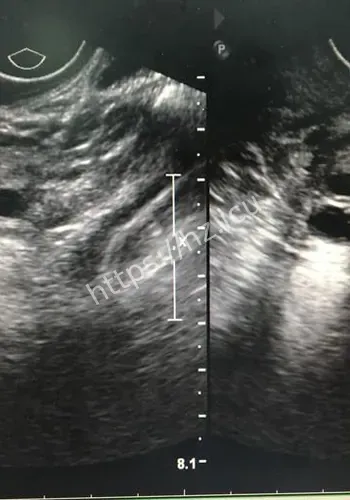

对观众来说,这类热点的影响,往往体现在它会不会改变自己对22厘米肌瘤致孕妇子的判断,或者会不会影响后续生活中的选择与讨论。检查揭示出一连串环环相扣的罕见致命危机:一个大小约为13.212.822.4厘米的巨大肌瘤,上缘顶至剑突,左右分别霸占整个腹腔,甚至超出超声探头的单一切面探测范围,并且提示血运丰富。因肌瘤推挤,子宫发生罕见的“箝闭”,即子宫体向后倾倒、死死卡在直肠窝内,宫底位置低于宫颈外口,整个子宫呈“倒置”状态。